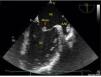

Primary cardiac tumors are rare in all age groups, with a reported prevalence of 0.001–0.03% in autopsy series. We report the case of a 37-year-old man, with no relevant medical history, who was admitted to the emergency department with sudden-onset right hemiparesis. Diagnostic studies revealed a small hypodense area in the left putamen and he was admitted to the stroke unit with a diagnosis of ischemic stroke. During investigation of the cause of stroke in such a young patient, he underwent transthoracic echocardiography, which showed a mass attached to the anterior leaflet of the mitral valve (Figure 1). Transesophageal echocardiography was then performed to clarify the picture, which confirmed a small echodense pedunculated mass, 0.5 cm2 in size, with well-defined borders, features typical of a fibroelastoma (Figures 2 and 3), attached to the atrial surface of the anterior mitral valve leaflet without causing mitral regurgitation (Figure 4). The rest of the echocardiographic examination revealed an estimated left ventricular ejection fraction of 65% and no other valvular abnormalities. The patient was subsequently referred to the cardiothoracic surgery center for surgical excision of the mass. Macroscopic examination showed a 0.6-cm whitish spiculated nodule with a soft elastic consistency. Histopathological study revealed cardiac myxoma. We present this case to highlight the unusual presentation, particularly its echocardiographic features.

Transesophageal echocardiogram in long-axis view, showing an echodense pedunculated mass adhering to the atrial face of the anterior mitral valve leaflet. The left atrial appendage can also be seen, with no evidence of thrombus. AAE: left atrial appendage; AE: left atrium; VE: left ventricle.